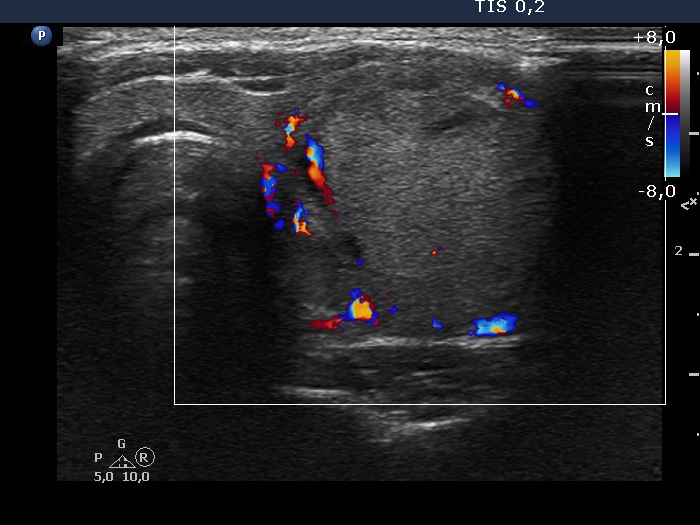

The echogenicity of the nodule - case 2075 (ultrasonographic picture 6)

Left lobe, transverse view, color Doppler mode.